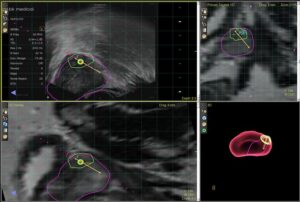

«Фьюжн» биопсия представляет собой сочетание данных микро-ультразвука и магнитно-резонансной томографии (МРТ) на платформе ExactVu с микро-ультразвуком. Эта технология помогает урологам выполнять целенаправленную биопсию конкретных участков простаты, которые подозрительны и требуют биопсии.

Высококвалифицированные специалисты центра, благодаря высокому разрешению технологий, используют одновременный контроль МРТ и микро-ультразвука для проведения целенаправленных биопсий подозрительных участков и достижения 100%-ной диагностики рака простаты, что практически невозможно при традиционных биопсиях. Процедура требует такой же подготовки, как и стандартная биопсия простаты, проводится за один день и не требует госпитализации.

Эта технология позволяет нашим специалистам находить скрытые опухоли, которые могут не быть выявлены при традиционных биопсиях простаты. Поскольку аппарат микро-ультразвука специально разработан для исследования простаты и его технология основана на совершенствовании визуализации, «Фьюжн» биопсия, объединяя данные МРТ и микро-ультразвука, предлагает совершенно новый уровень разрешения, что обеспечивает:

- Очень точную дифференциацию подозрительных тканей

- Очень точную визуализацию подозрительных участков

- Точную нацеливание на подозрительные участки

- Выполнение целенаправленной биопсии в реальном времени